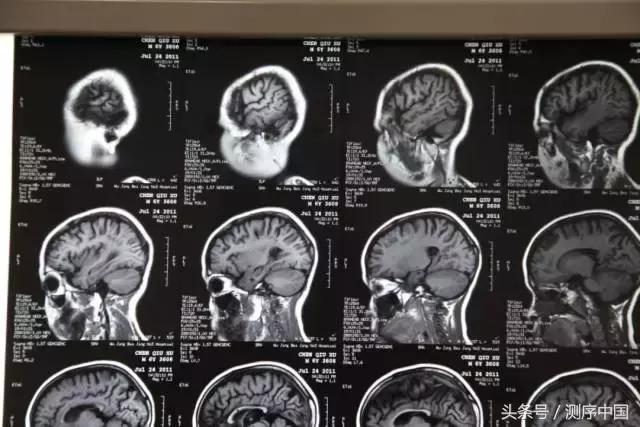

男孩,9岁,身高121.5cm(矮小),体重27.8kg;出生史无特殊;1岁会走路,2岁会说话,3岁上幼儿园;5岁时家长感觉明显退步;就诊时表达意思不清楚,好动,不与人沟通,不会写字;辅助检查:8岁IQ小于40;染色体正常;血尿串联正常;甲状腺功能正常,生长激素完全缺乏;MECP2 Rett综合征基因检测未见异常;基因芯片检测未见异常;脆性X综合征未见异常;在某医院给予干细胞脑注射治疗,效果欠佳,9岁时智力接近于0;辅助检查:脑电图正常;脑MRI:右额叶多发软化灶,双侧脑室宽,脑沟增宽。